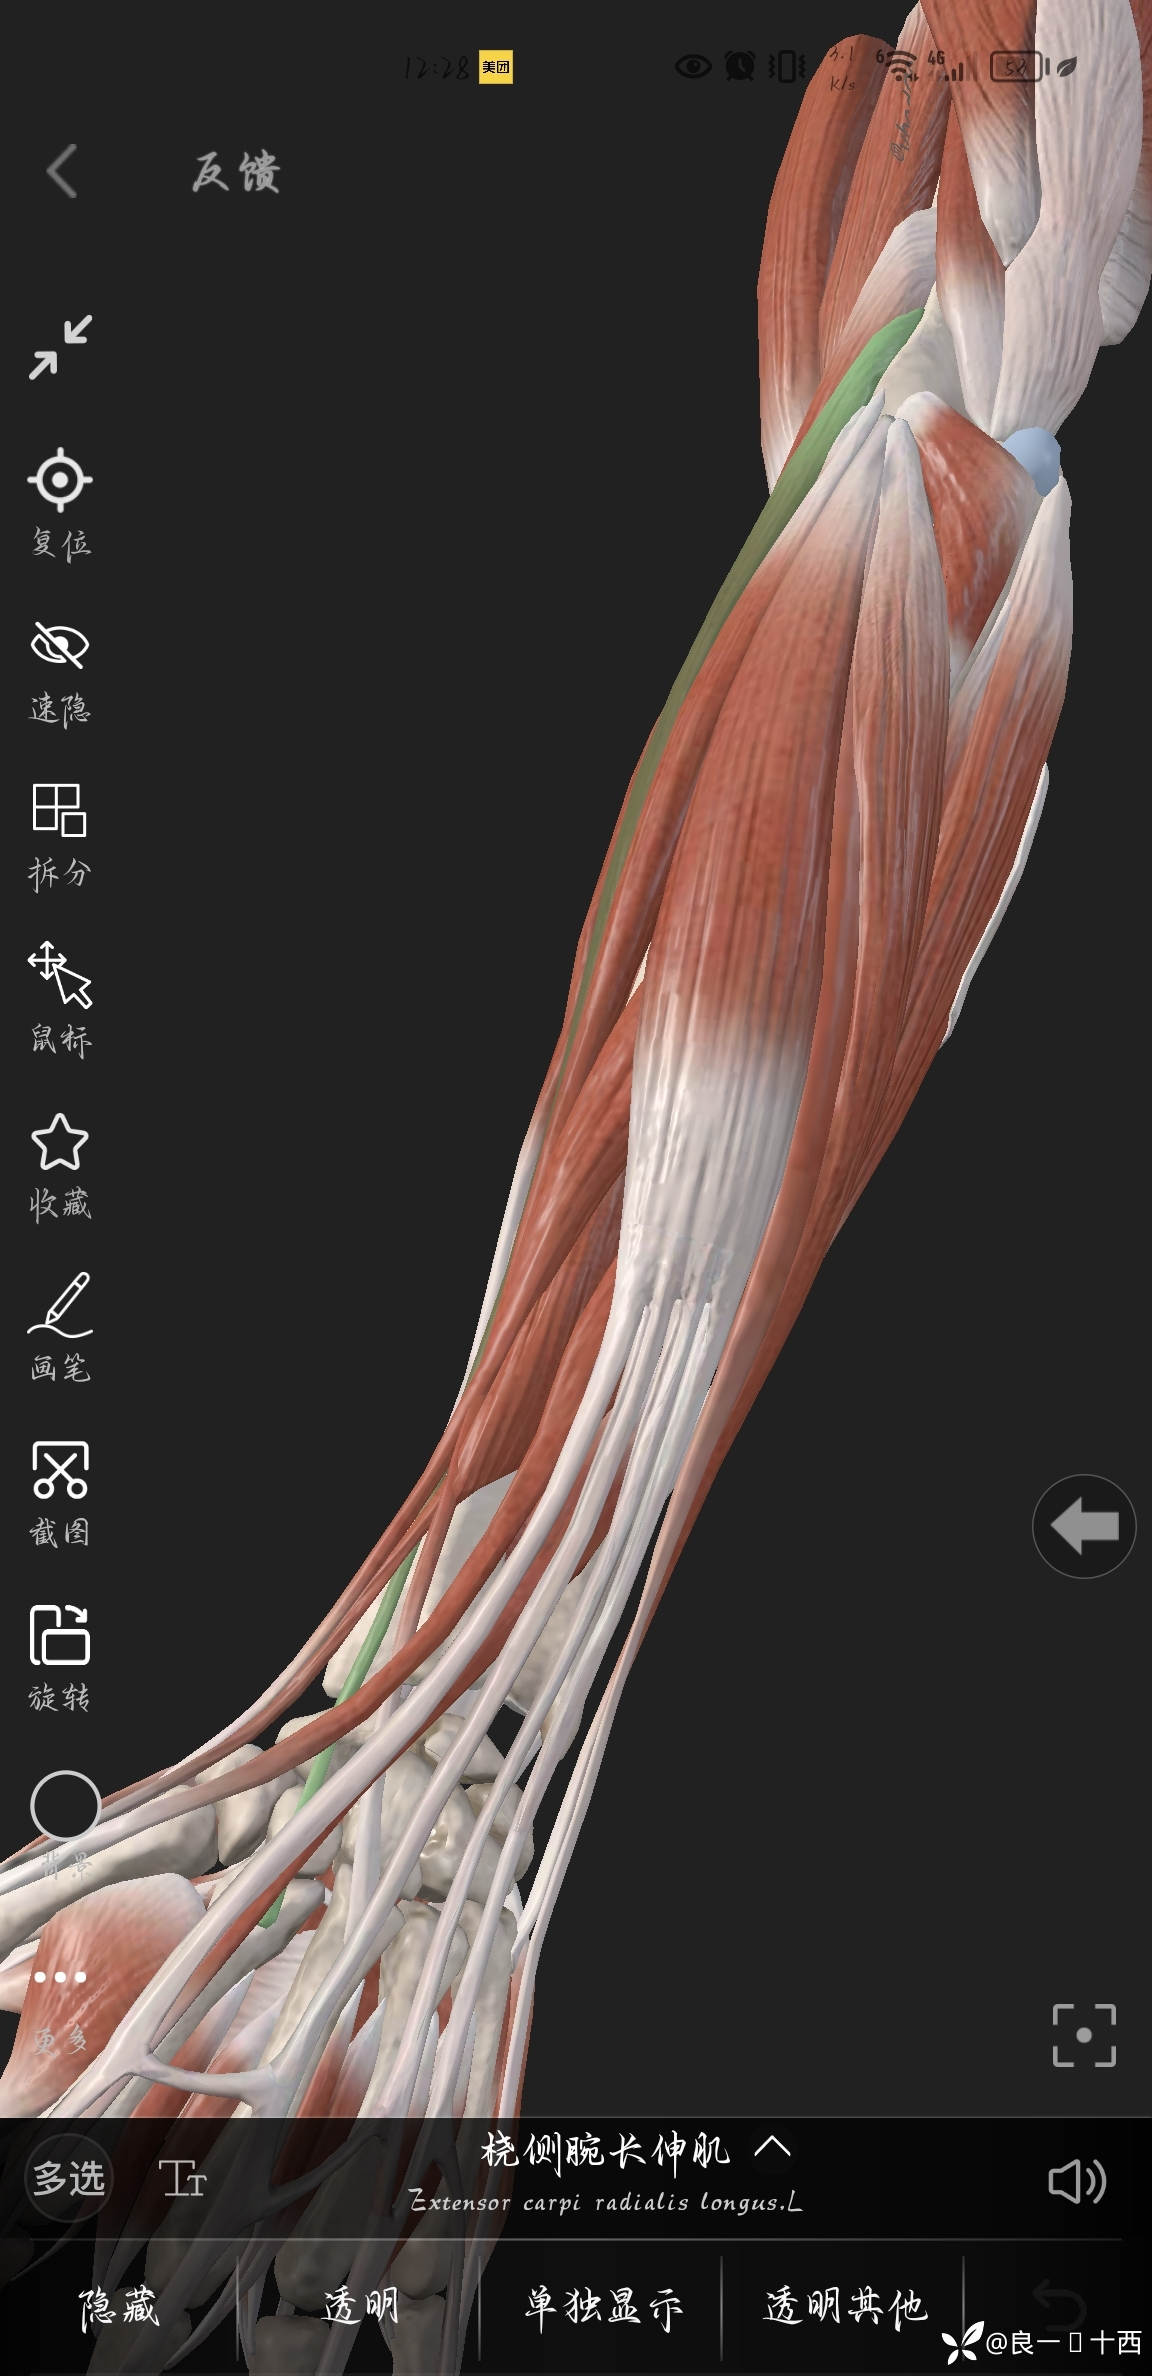

断裂的两根肌腱及位置如下图所示

好家伙,还犹豫什么呢?果断两侧延长切口,逐层小心分离暴露,先找出并且保护好桡神经浅支,头静脉,然后自鞘管背侧远端找出了部分损伤的拇长伸肌腱,

一开始想从鞘管两段里面用止血钳看看能不能把断裂回缩的肌腱给拉出来,减少创伤,可是试了二十来分钟,也没有全部拉出来,得嘞,沿着鞘管纵形切开,终于是各自找到了断裂的桡侧腕长伸肌腱跟桡侧腕短伸肌腱,松一口气,把心里的石头放下了肚子里,使用缝线标记。

虽然说是第一次做这个地方手术,可我毕竟花了两个小时,感觉主任跟老师们来做,估计要比我快上一倍的时间,不禁感叹还是解剖没有学习到位,手术过程中,犹犹豫豫,磨磨蹭蹭,不敢下刀,但是也比较开心的是通过对这附近的解剖有了更深刻的理解,我还差的远,还差的多,笨鸟一只,吾之医道,道阻且长,还需溯游从之,不可盲目,要专心!要耐心!总结经验,总结方法才对。